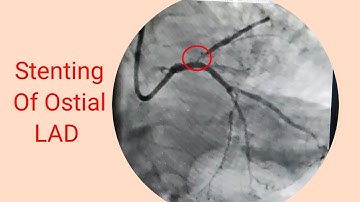

ostial LAD CTO